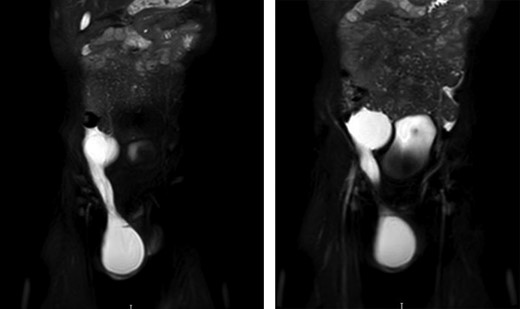

Persistence of the hydrocele and a differential diagnosis of lymphatic malformation were discussed by a multidisciplinary team and an MRI scan was advised. This displayed a large fluid filled structure adjacent to the bladder which was not present when the USS was conducted. The structure tracked down the inguinal canal to the right-sided scrotal hydrocele (Fig. 2).